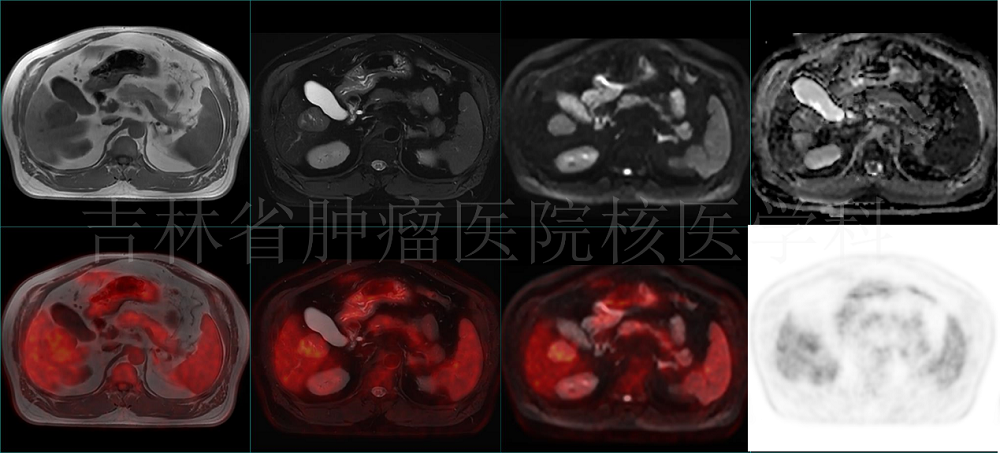

病例1 PET/MR 肝占位定性:肝右叶占位,T1WI呈低信号,T2压脂呈混杂高信号,DWI呈高信号,ADC值减低,伴糖代谢增高,提示恶性(病理结果:HCC)